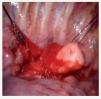

Mujer de 34 años sin antecedentes personales patológicos, quien consulta con historia de 3 meses de evolución de disfagia progresiva. Estudio baritado esofágico reveló compresión extrínseca en tercio medio (Imagen 1). La endoscopia alta mostró una lesión que ocluía 50% de la luz esofágica con mucosa intacta. La tomografía axial computada con contraste esofágico reveló una lesión intramural, no adherida a planos adyacentes a nivel de la pared esofágica lateral derecha en el tercio medio, cercano al cayado aórtico (Imagen 2). A la paciente se le realizó enucleación toracoscópica con abordaje lateral derecho de tumoración esofágica en tercio medio sin complicaciones (Fotos 1 y 2). El informe histopatológico reportó GIST (Gastrointestinal Stromal Tumor) esofágico CD117 (+). Estudio contrastado de control sin estrecheces ni escape. Fue dada de alta al cuarto día posoperatorio.

Foto 1. Enucleación toracoscópica de la tumoración esofágica.